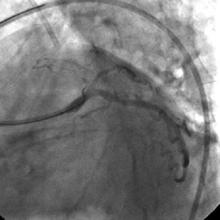

Angiography

1) RCA: Discrete severe mid stenosis (Figure 1)